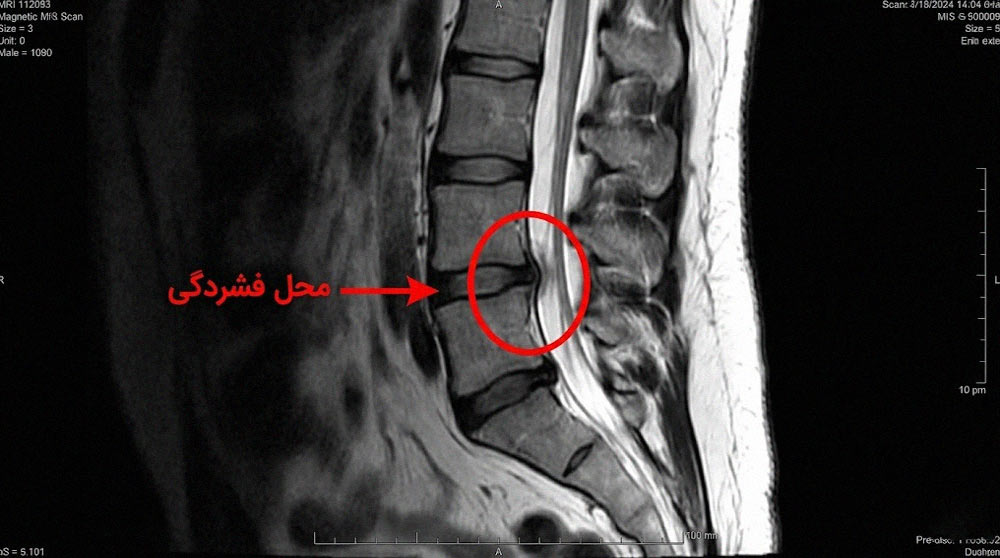

- تصویربرداری مخصوص از ستون فقرات: شامل سی تی اسکن و ام آر آی که نگاه دقیق تری به نخاع و ساختارهای اطراف آن دارند.

MRI: استاندارد طلایی تشخیص ام آر آی (بدون کنتراست) روش انتخابی تصویربرداری است چون حساسیت بالایی (۹۳ درصد) و اختصاصیت بالایی (۹۷ درصد) دارد. دقت کلی ام آر آی در تشخیص فشردگی نخاع متاستاتیک ۹۵ درصد است. علاوه بر این، ام آر آی نشان می دهد آیا فشردگی مربوط به نخاع است یا ریشه های عصبی، و اطلاعات مفیدی درباره پایداری ستون فقرات ارائه می دهد. چون علائم با سطح فشردگی همبستگی ضعیفی دارند و فشردگی نخاع می تواند همزمان در چند سطح رخ دهد، تصویربرداری کل ستون فقرات توصیه می شود.